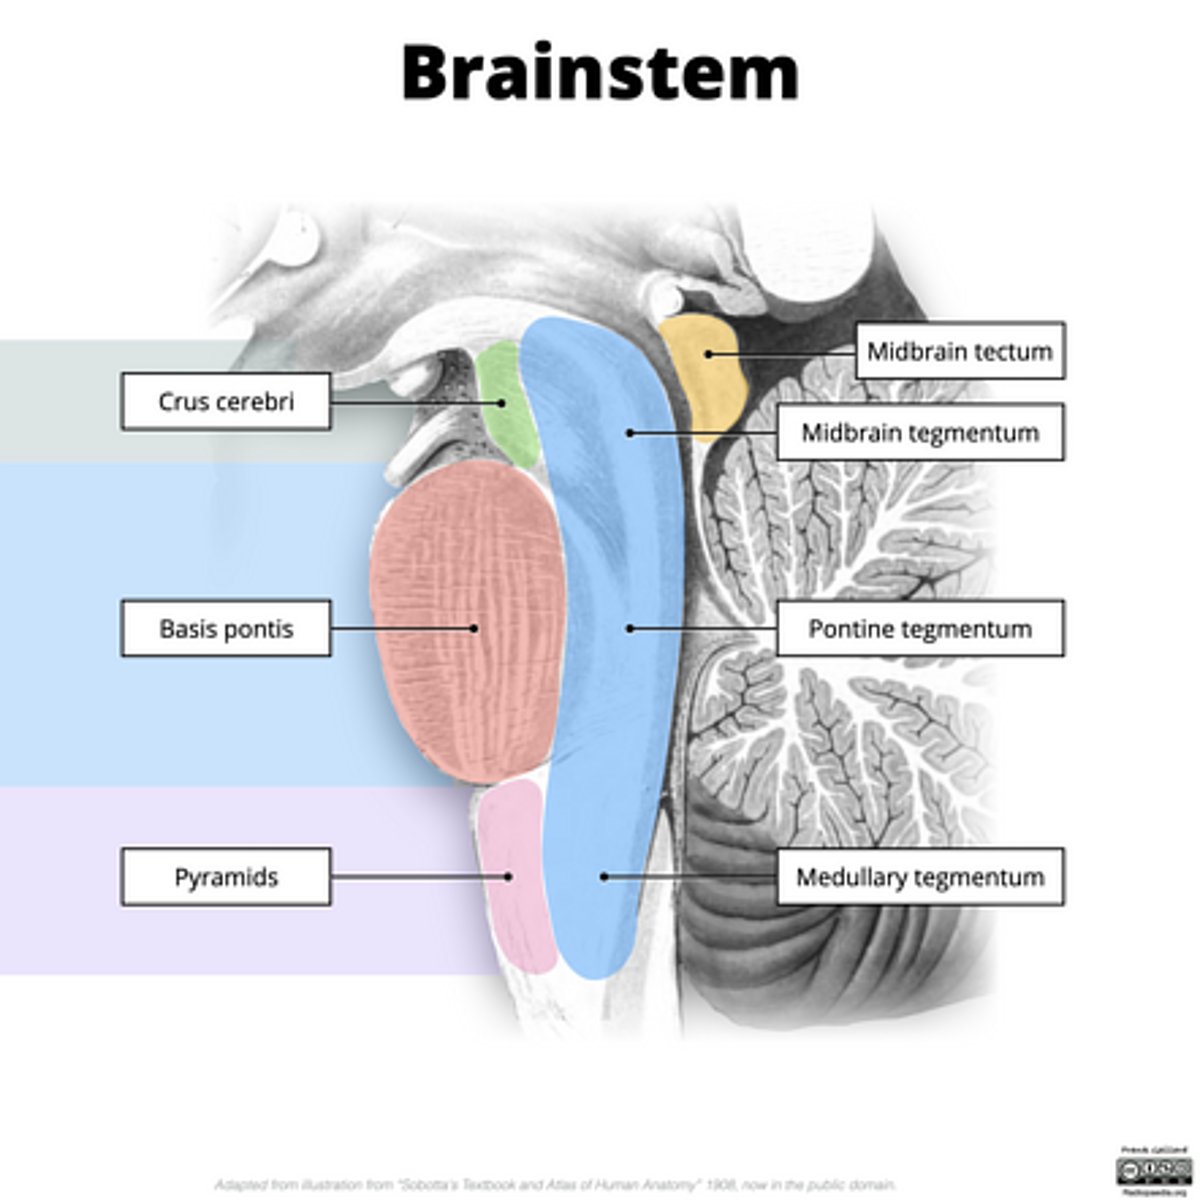

What is the tectum?

roof of the midbrain

What is the tegmentum?

floor of midbrain

What are the fibers of the tegmentum?

ascending fibers

What is the crus cerebri?

part of the cerebral peduncles which contain descending tracts

What are the fibers of the crus cerebri?

descending fibers

What leaves the peduncular fossa?

CN III